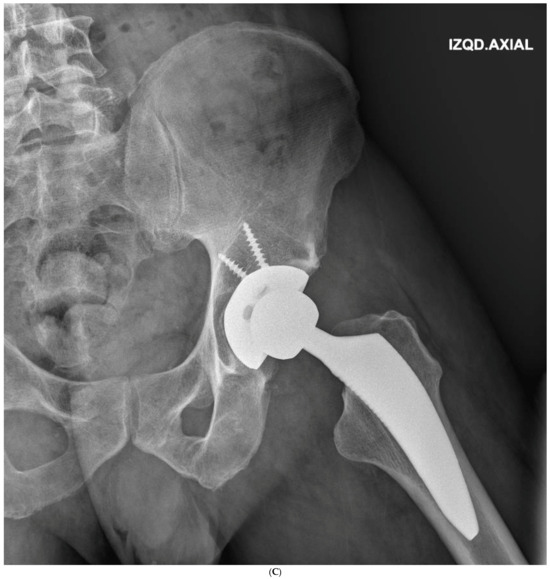

Figure 3.

(A) Preoperative anteroposterior X-ray. Left hip sustained a displaced femoral neck fracture. (B) Postoperative anteroposterior X-ray (SFS group). Both the short stem and acetabular cup appear well osseointegrated and stable at final follow-up. (C) Postoperative lateral X-ray (SFS group). The stem is osseointegrated and there is absence of radiolucent lines at bone-implant interface.